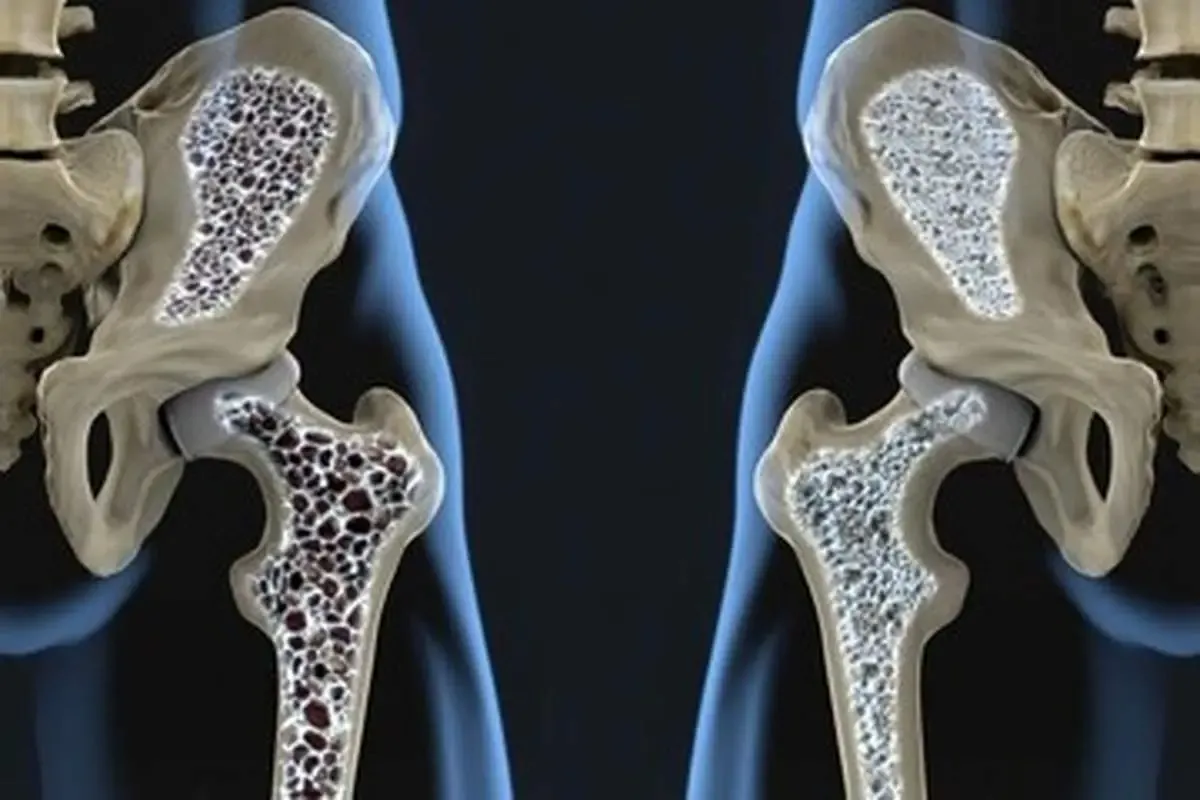

به گزارش آرمان ملی انلاین ، تراکم استخوانها آنقدر برای سلامت اهمیت دارد که کاهش آن حتی خطر مرگ را به همراه دارد. برای جلوگیری از پوکی استخوان از این غذاه استفاده کنید: